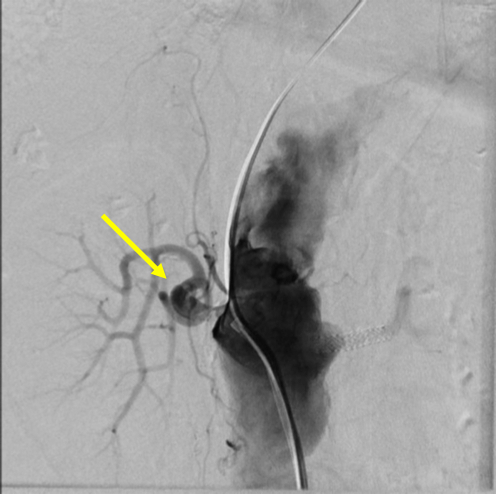

The patient was initially treated with non-invasive ventilation, a continuous nitroglycerin infusion, and IV furosemide with rapid improvement in her symptoms and vital signs. She was quickly transitioned to simple nasal cannula and oral antihypertensive medications; IV diuresis was continued. However, despite these initial improvements, her renal function steadily worsened over the subsequent days. Renal doppler ultrasound revealed an elevated right renal artery peak systolic velocity of 292 cm/sec with delayed acceleration times. After an interdisciplinary discussion, she underwent right renal artery angiography and drug-eluting stent placement.